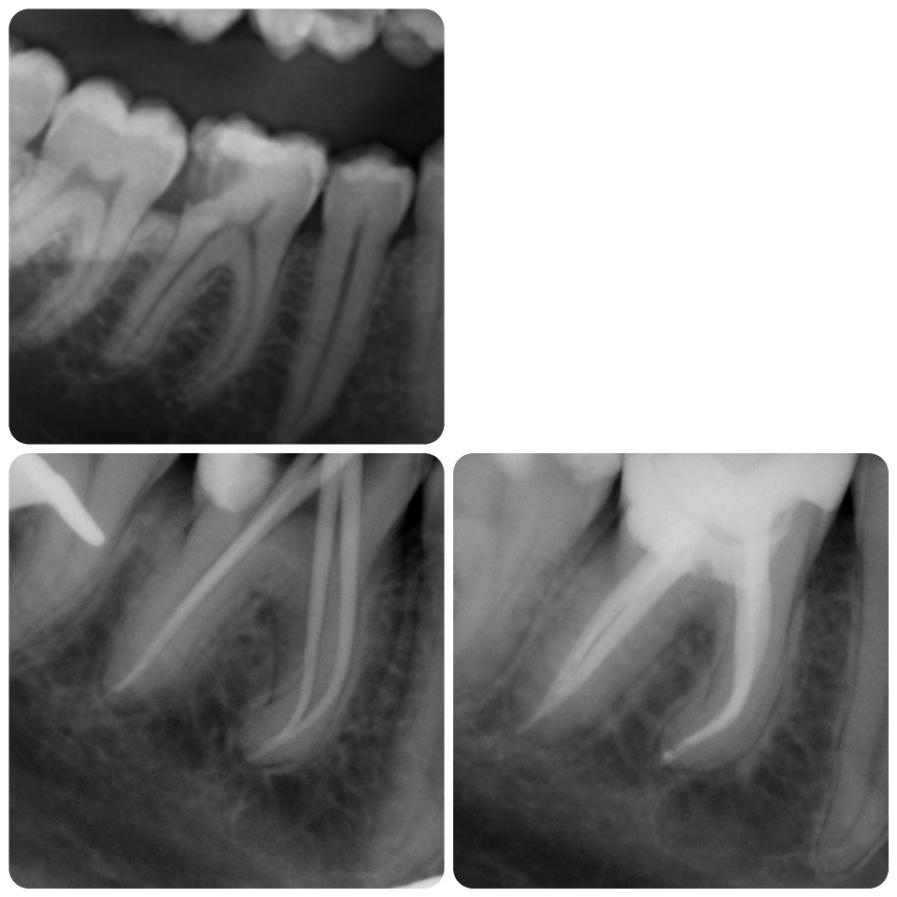

Leczenie kanałowe pierwotne

Konserwatywne leczenie torbieli korzeniowej (reendo – powtórne leczenie kanałowe).

Efekt po 6 miesiącach.

lek. stom. Aleksa Mucha